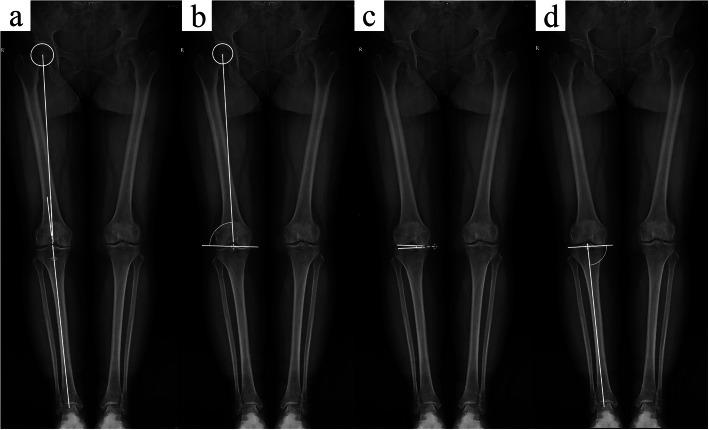

Forty-five patients (52 knees) who underwent KA-TKA in our hospital were included. Patient-specific instrumentation was used in 16 patients (16 knees), and conventional instruments with calipers and other special tools were employed in the other 29 patients (36 knees). The widths of the exposed resection bone surface at the middle (MIDexposure) and distal (DISexposure) levels on the lateral trochlea were measured as dependent variables, whereas the hip-knee-ankle angle (HKAA), mechanical lateral distal femoral angle (mLDFA), joint line convergence angle (JLCA), medial proximal tibial angle (MPTA) and transepicondylar axis angle (TEAA) were measured as independent variables. Correlation analysis and subsequent linear regression were conducted among the dependent variables and various alignment parameters of the tibiofemoral joint.

The incidence of undercoverage of the lateral trochlear resection surface was 86.5 % with MIDexposure and DISexposure values of 2.3 (0-6 mm) and 2.0 (0-5 mm), respectively. The widths of the two levels of exposed bone resection were significantly correlated with mLDFA and HKAA but were not related to TEAA.